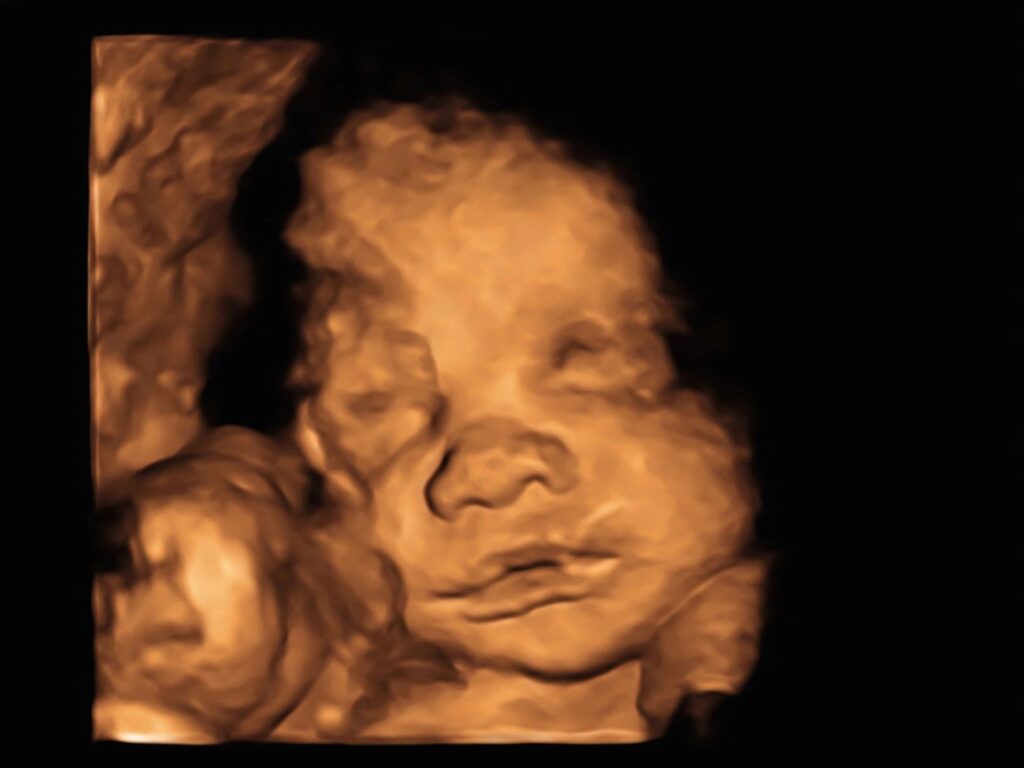

Image by nata_zhekova and licensed via Adobe Stock.